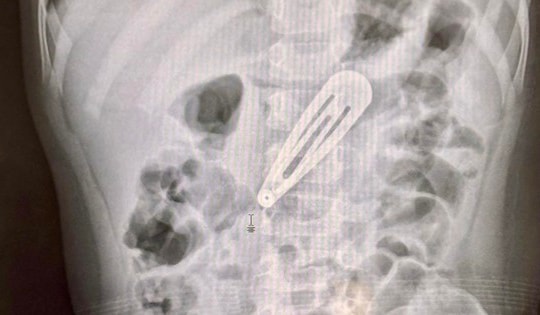

Trong quá trình nội soi, bác sĩ phát hiện dị vật là hạt hướng dương gây che lấp gần hoàn toàn đường thở vị trí ở ngay phế quản gốc.

Dị vật là hạt hướng dương gây che lấp gần hoàn toàn đường thở vị trí ở ngay phế quản gốc.